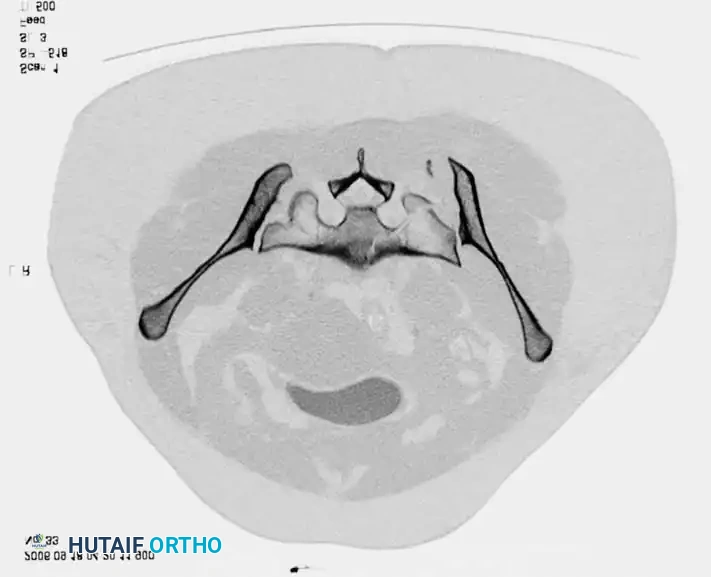

Radiographic Evaluation

Standard evaluation begins with an Anteroposterior (AP) pelvis radiograph. However, definitive surgical planning requires specialized views and advanced imaging.

• Inlet View: Directed 45 degrees caudad. Best evaluates anterior-posterior translation, internal/external rotation, and sacral impaction.

• Outlet View: Directed 45 degrees cephalad. Best evaluates vertical translation and sacral foraminal anatomy.

• CT Scan: The gold standard for evaluating posterior ring injuries, sacral dysmorphism, and preoperative planning for percutaneous fixation.